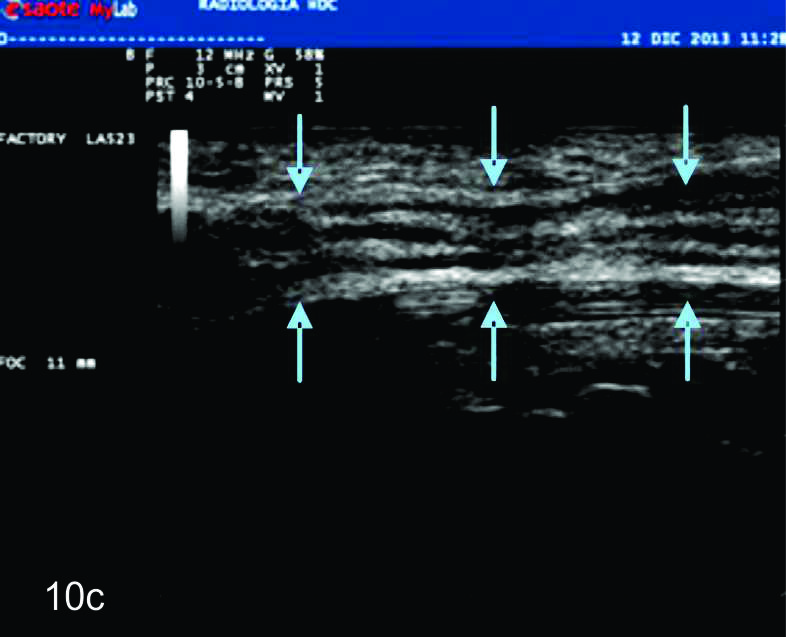

Figura 10

Hamartoma fibrolipomatoso del nervio mediano

A y B, cortes transversales en antebrazo y puño, las flechas azules señalan al nervio mediano aumentado de tamaño con fascículos engrosados. C- Corte longitudinal con hallazgos similares en plano longitudinal del nervio (flechas azules).